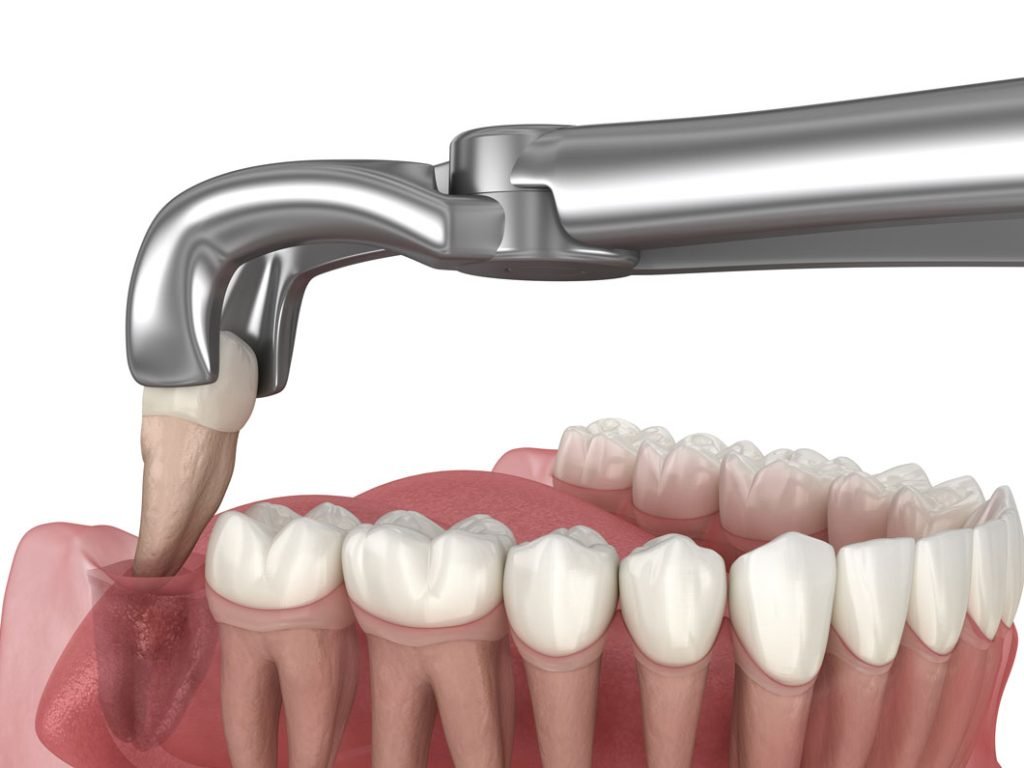

surgical tooth extraction

Surgical teeth removal is required when a tooth is not easily accessible, such as when it is broken below the gum line or impacted. This procedure may involve a small incision to safely remove the tooth.

The Extraction Procedure

Local anaesthesia is applied to numb the area. The tooth is then carefully loosened and removed using controlled techniques to minimise trauma to surrounding tissue.